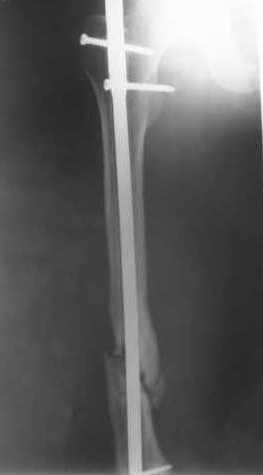

В приложении пример, дистальный отломок пружинил кзади. Два винта потому, что первый оказался чуть кпереди и не упирался в гвоздь.